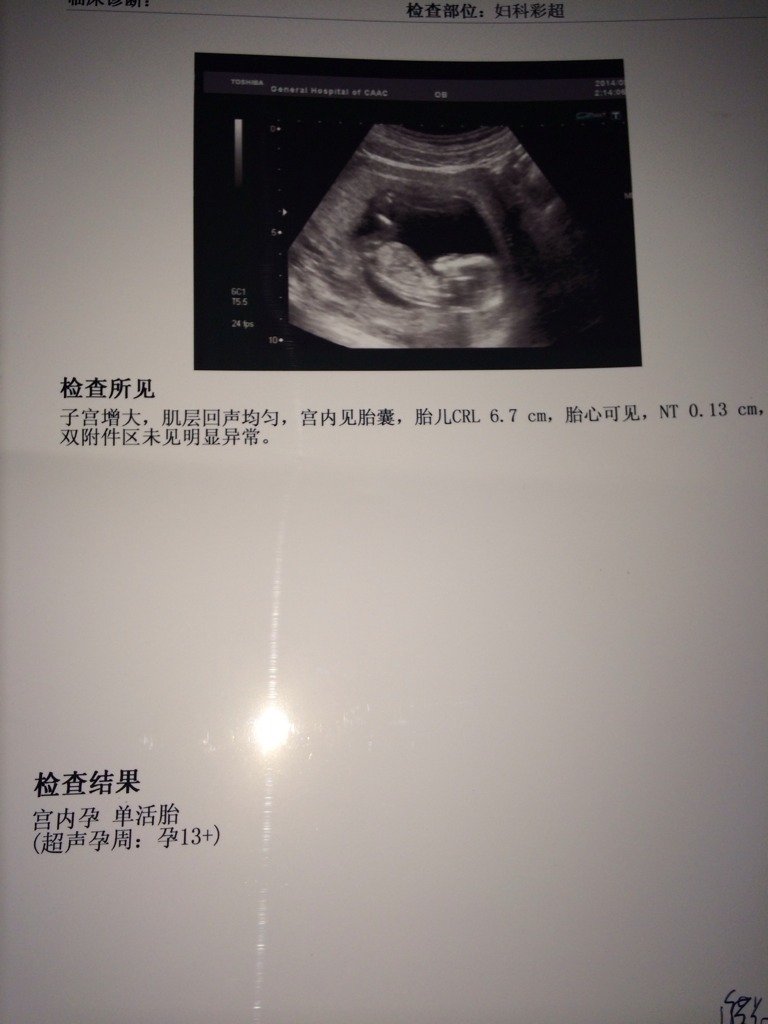

也不知道这个B超做的好不好,胎儿稳不稳,医生也没有说,哎~ 也不知道这个B超做的好不好,胎儿稳不稳,医生也没有说,哎~ 点击展开 安于╰宿命 2014-08-18 15:44 为您推荐: 其他回答 结果还行的,没有什么问题的啊,孕周应该和你实际的差不多吧,以后定期的复查就是了 我是学霸306 2014-08-18 17:18 没说就是正常 柔儿 2014-08-18 16:39 如果胎儿不好医生会建议你流掉的,所以没说说明宝宝发育的很好 没有温度的感情0℃ 2014-08-18 16:02 正常!以后再有问题就想着问医生 ︷゛兮哩糊涂 2014-08-18 15:52 挺好的 缘分天空_jA6R 2014-08-18 15:48 加载更多 相关问题 怀孕65天,今天做b超,医生说前壁有一肿瘤,2 7mm,胎儿一切正常,不知道以后会不会对胎儿有影响 做b超医生说孕囊大,胎儿小,还来了比智高,真不知道现在医生都是干什么的